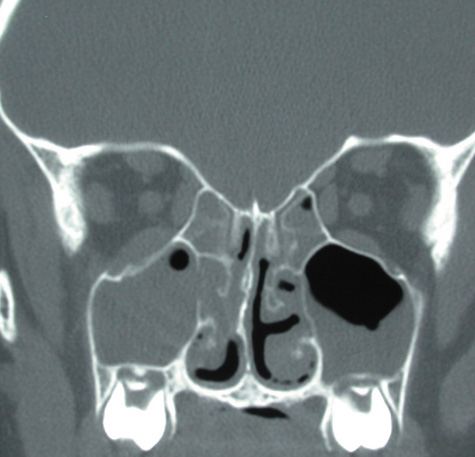

Routine skull films and polytomography have been supplanted by CT in the evaluation of patients with orbital cellulitis.57 CT allows the clinician to differentiate a preseptal cellulitis from an orbital cellulitis.58 If orbital cellulitis has resulted from adjacent intercurrent sinus infection, the diagnosis can be made and the extent of the sinus disease estimated. Sinuses may show changes of osteomyelitis with blurring of the osseous margins of the sinuses, air–fluid levels, or inflammatory tissue within the normally aerated sinus.59 Central nervous system complications can be assessed by neuroimaging, and progression of disease can also be monitored.58

CT should be performed using thin-section (2–4 mm) high-resolution scanning with multiple views of both bone and soft tissue detail.53 Axial and coronal views should be obtained; in one-third of patients with subperiosteal abscesses, the abscess was seen in the coronal sections only.18 Helical CT is a fairly new technology that allows increased resolution with decreased imaging time.60 This type of scan may be especially beneficial in children because of the ability to obtain good imaging with a shorter imaging time.60 elica He HhIntravenous contrast material is not advocated at all centers because there is intrinsically high contrast between infectious changes and orbital fat. However, some authors believe that it is essential to the diagnosis, and it thus remains the preference of the individual clinician, as well as the neuroradiologist.22,59,62

With preseptal inflammation, CT demonstrates soft tissue swelling of the eyelids and tissue adjacent to the orbital septum (Fig. 15). The orbit is not involved, and usually the sinuses do not show evidence of inflammation. The distinction between inflammatory preseptal cellulitis and edema cannot be made.63

Fig. 15. Computed tomography showing preseptal cellulitis of left eye. Note that all swelling is anterior to the orbital septum.